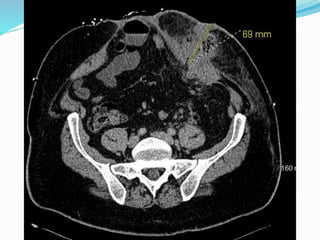

Parastomal hernia

 Incidence is unknown

due to underreporting

and difficult dx.

 Estimated to be between

20-80%

 More frequent with

colostomy than

ileostomy

 Cingi et al

 23 patients

 Patient examination

(PE) detected PSH in

52%

 CT detected total of

78%